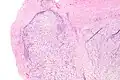

| Micrograph of nodular fasciitis showing the haphazard arrangement of cells (tissue culture-like pattern). H&E stain. | |

The microscopic histopathology of hematoxylin and eosin stained nodular fasciitis tumors consists of spindle-shaped myofibroblastic cells.[8] These cells are in a myxoid or a collagenous (high content of collagen fibers) tissue background. The neoplastic myofibroblasts are arranged in whorls and/or short bundles. These cells may show high rates of replicating as judged by their mitotic index, but these mitoses are normal in appearance. The tumor tissues often contain red blood cells, lymphocytes, and giant osteoclast-like cells, and may contain sites of bone-like tissue.[10] NF is sometimes classified into three subtypes based on its predominant histopathological pattern: myxoid or reactive (type I), cellular (type II), and fibrous (type III).[4] These patterns appear related to the duration of the lesion, with the myxoid variant tending to have the shortest duration and the cellular and fibrous variants tending to have progressively longer durations.[14] Immunohistochemical analyses indicate that the cells in NF usually express smooth muscle actin, muscle specific actin, and vimentin proteins but generally do not express CD34, S-100 protein, desmin, trypsin, factor VIII, F4/80, or HLA-DR1 proteins.[10] Uncommonly, the cells in NF tumors express the CD68 (a histiocyte-specific marker) protein.[4]